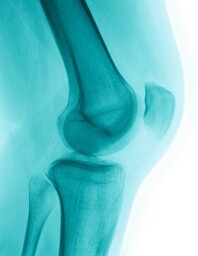

The crook of your arm contains a joint. Joints are places where two bones connect with each other. The elbow joint makes it possible for us to bend and rotate our arms. It also prevents the arm from bending backwards.

The pelvis protects your intestines. The large leg bones are called the femur, the tibia and the fibia. They are joined together by the knee joint, which is protected by a bone called the patella.